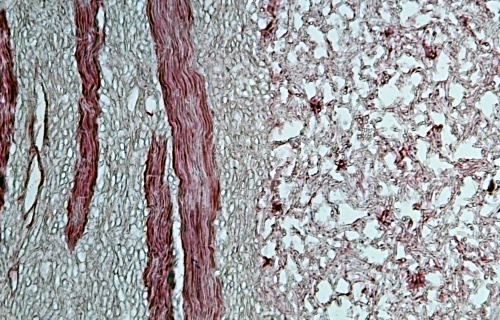

果真如此吗?我将冬虫夏草制成切片,到显微镜下观察一下。(见图2)

图2 红色是虫体的肌肉(平滑肌),浅蓝色竹节样细丝是霉菌菌丝